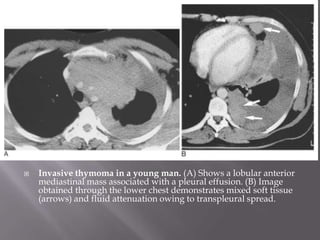

 Invasive thymoma in a young man. (A) Shows a lobular anterior

mediastinal mass associated with a pleural effusion. (B) Image

obtained through the lower chest demonstrates mixed soft tissue

(arrows) and fluid attenuation owing to transpleural spread.